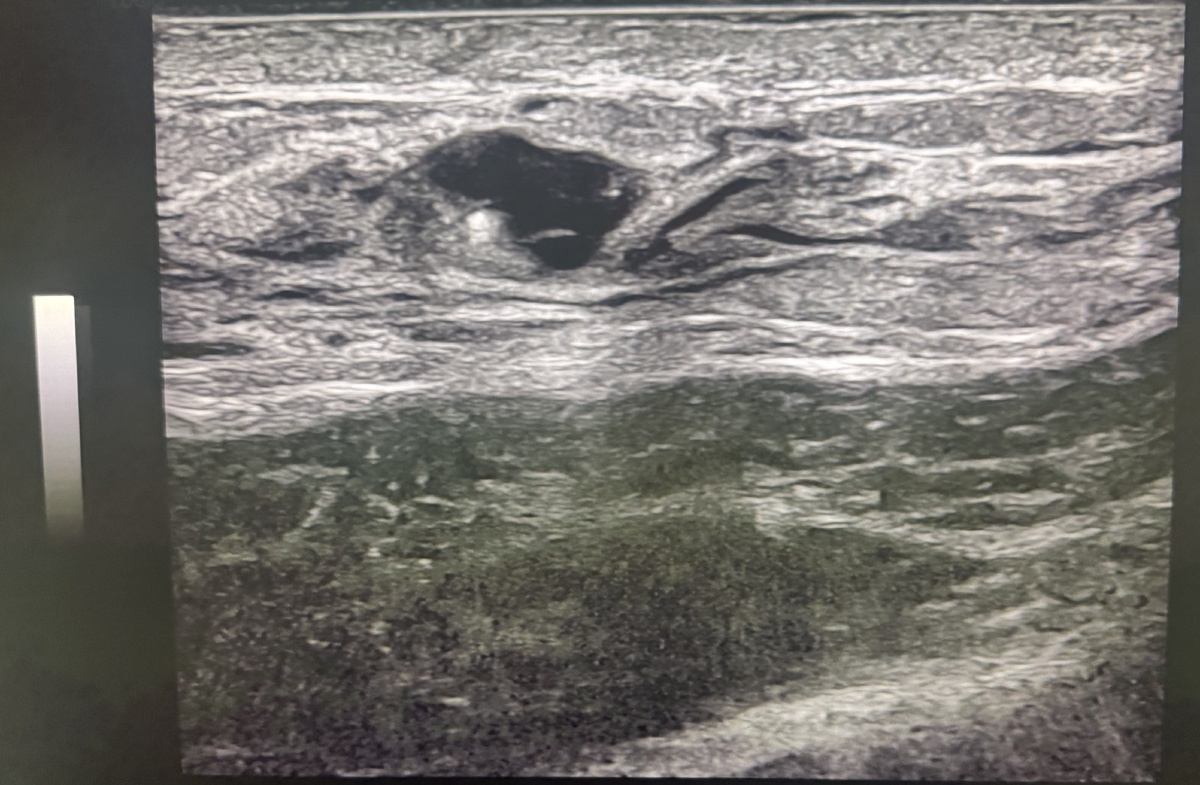

На фото ниже представлен снимок УЗИ молочных желез, на котором определяется киста с перегородками. В стенке кисты четко виден округлое белое включение - микрокальцинат.

Размеры кисты 7,5 х 4 мм, а диаметр самого микрокальцината при этом всего 0,8 мм.